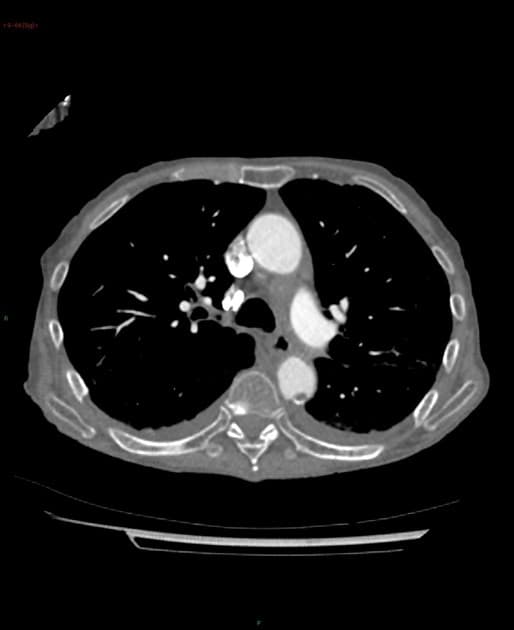

Có một khối mô mềm giới hạn không rõ (ill-defined soft tissue mass) gần như chiếm toàn bộ tâm nhĩ trái, xuyên qua vách liên nhĩ vào tâm nhĩ phải và dường như lồi vào tĩnh mạch chủ dưới (inferior vena cava - IVC) gần đoạn đầu. Khối này có độ cản âm tương đối đồng nhất (homogeneous hypoattenuation). Không thấy tăng quang đáng kể, không thấy hình ảnh hoại tử trung tâm hay vôi hóa.

Cũng ghi nhận tràn dịch màng ngoài tim mức độ trung bình, đo được độ sâu tối đa 4 cm, chủ yếu tập trung dọc theo bờ dưới của tim; chưa rõ có tổ chức đặc không tăng quang trong khoang màng ngoài tim hay không.

Đoạn gốc tĩnh mạch phổi dưới trái bị hẹp nhẹ. Nhánh sau bên của động mạch vành phải dường như bị bao quanh bởi mô mềm.

Một vài nốt nhỏ không đặc hiệu và xẹp phổi (atelectasis) dạng dải ở thuỳ dưới phổi trái. Phổi còn lại rõ. Không có tràn dịch màng phổi (pleural effusion). Không thấy tổn thương xương nghi ngờ.

Kết luận: Hình ảnh phù hợp với khối u tim khu trú ở tâm nhĩ trái, xuyên qua vách liên nhĩ vào tâm nhĩ phải, kèm tràn dịch màng ngoài tim và lan vào tĩnh mạch chủ dưới (IVC extension). Đặc điểm này không điển hình cho myxoma nhĩ; cần cân nhắc sarcoma, di căn (metastasis), lymphoma hoặc huyết khối (thrombus).